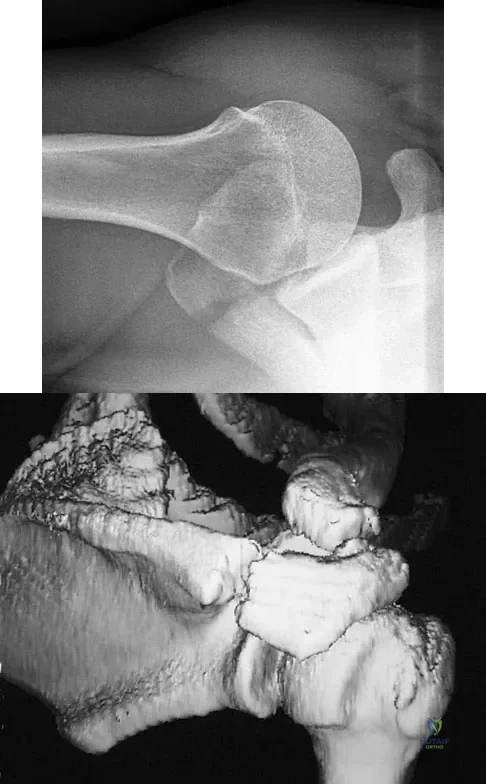

Question 88

Figure 54 shows the preoperative radiograph of a 45-year-old woman who is considering total hip arthroplasty with her orthopaedic surgeon. What femoral characteristic is a typical concern in this patient?

Explanation